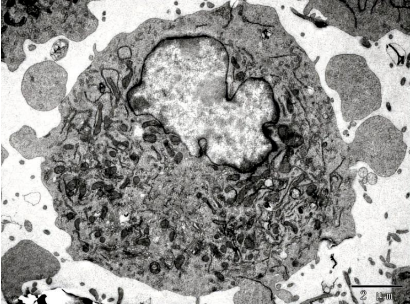

10、細胞的超微結構——細胞核

細胞核(nucleus)是真核細胞內最大、最重要的細胞結構,是細胞遺傳與代謝的調控中心,是真核細胞區別于原核細胞最顯著的標志之一(極少數真核細胞無細胞核,如哺乳動物的成熟的紅細胞,高等植物成熟的篩管細胞等)。它主要由核膜(nuclear membrane)、染色質(chromatin)、核仁(nucleolus)、核基質(nuclear matrix) 等組成。細胞核是細胞內遺傳信息的儲存、復制和轉錄的主要場所。